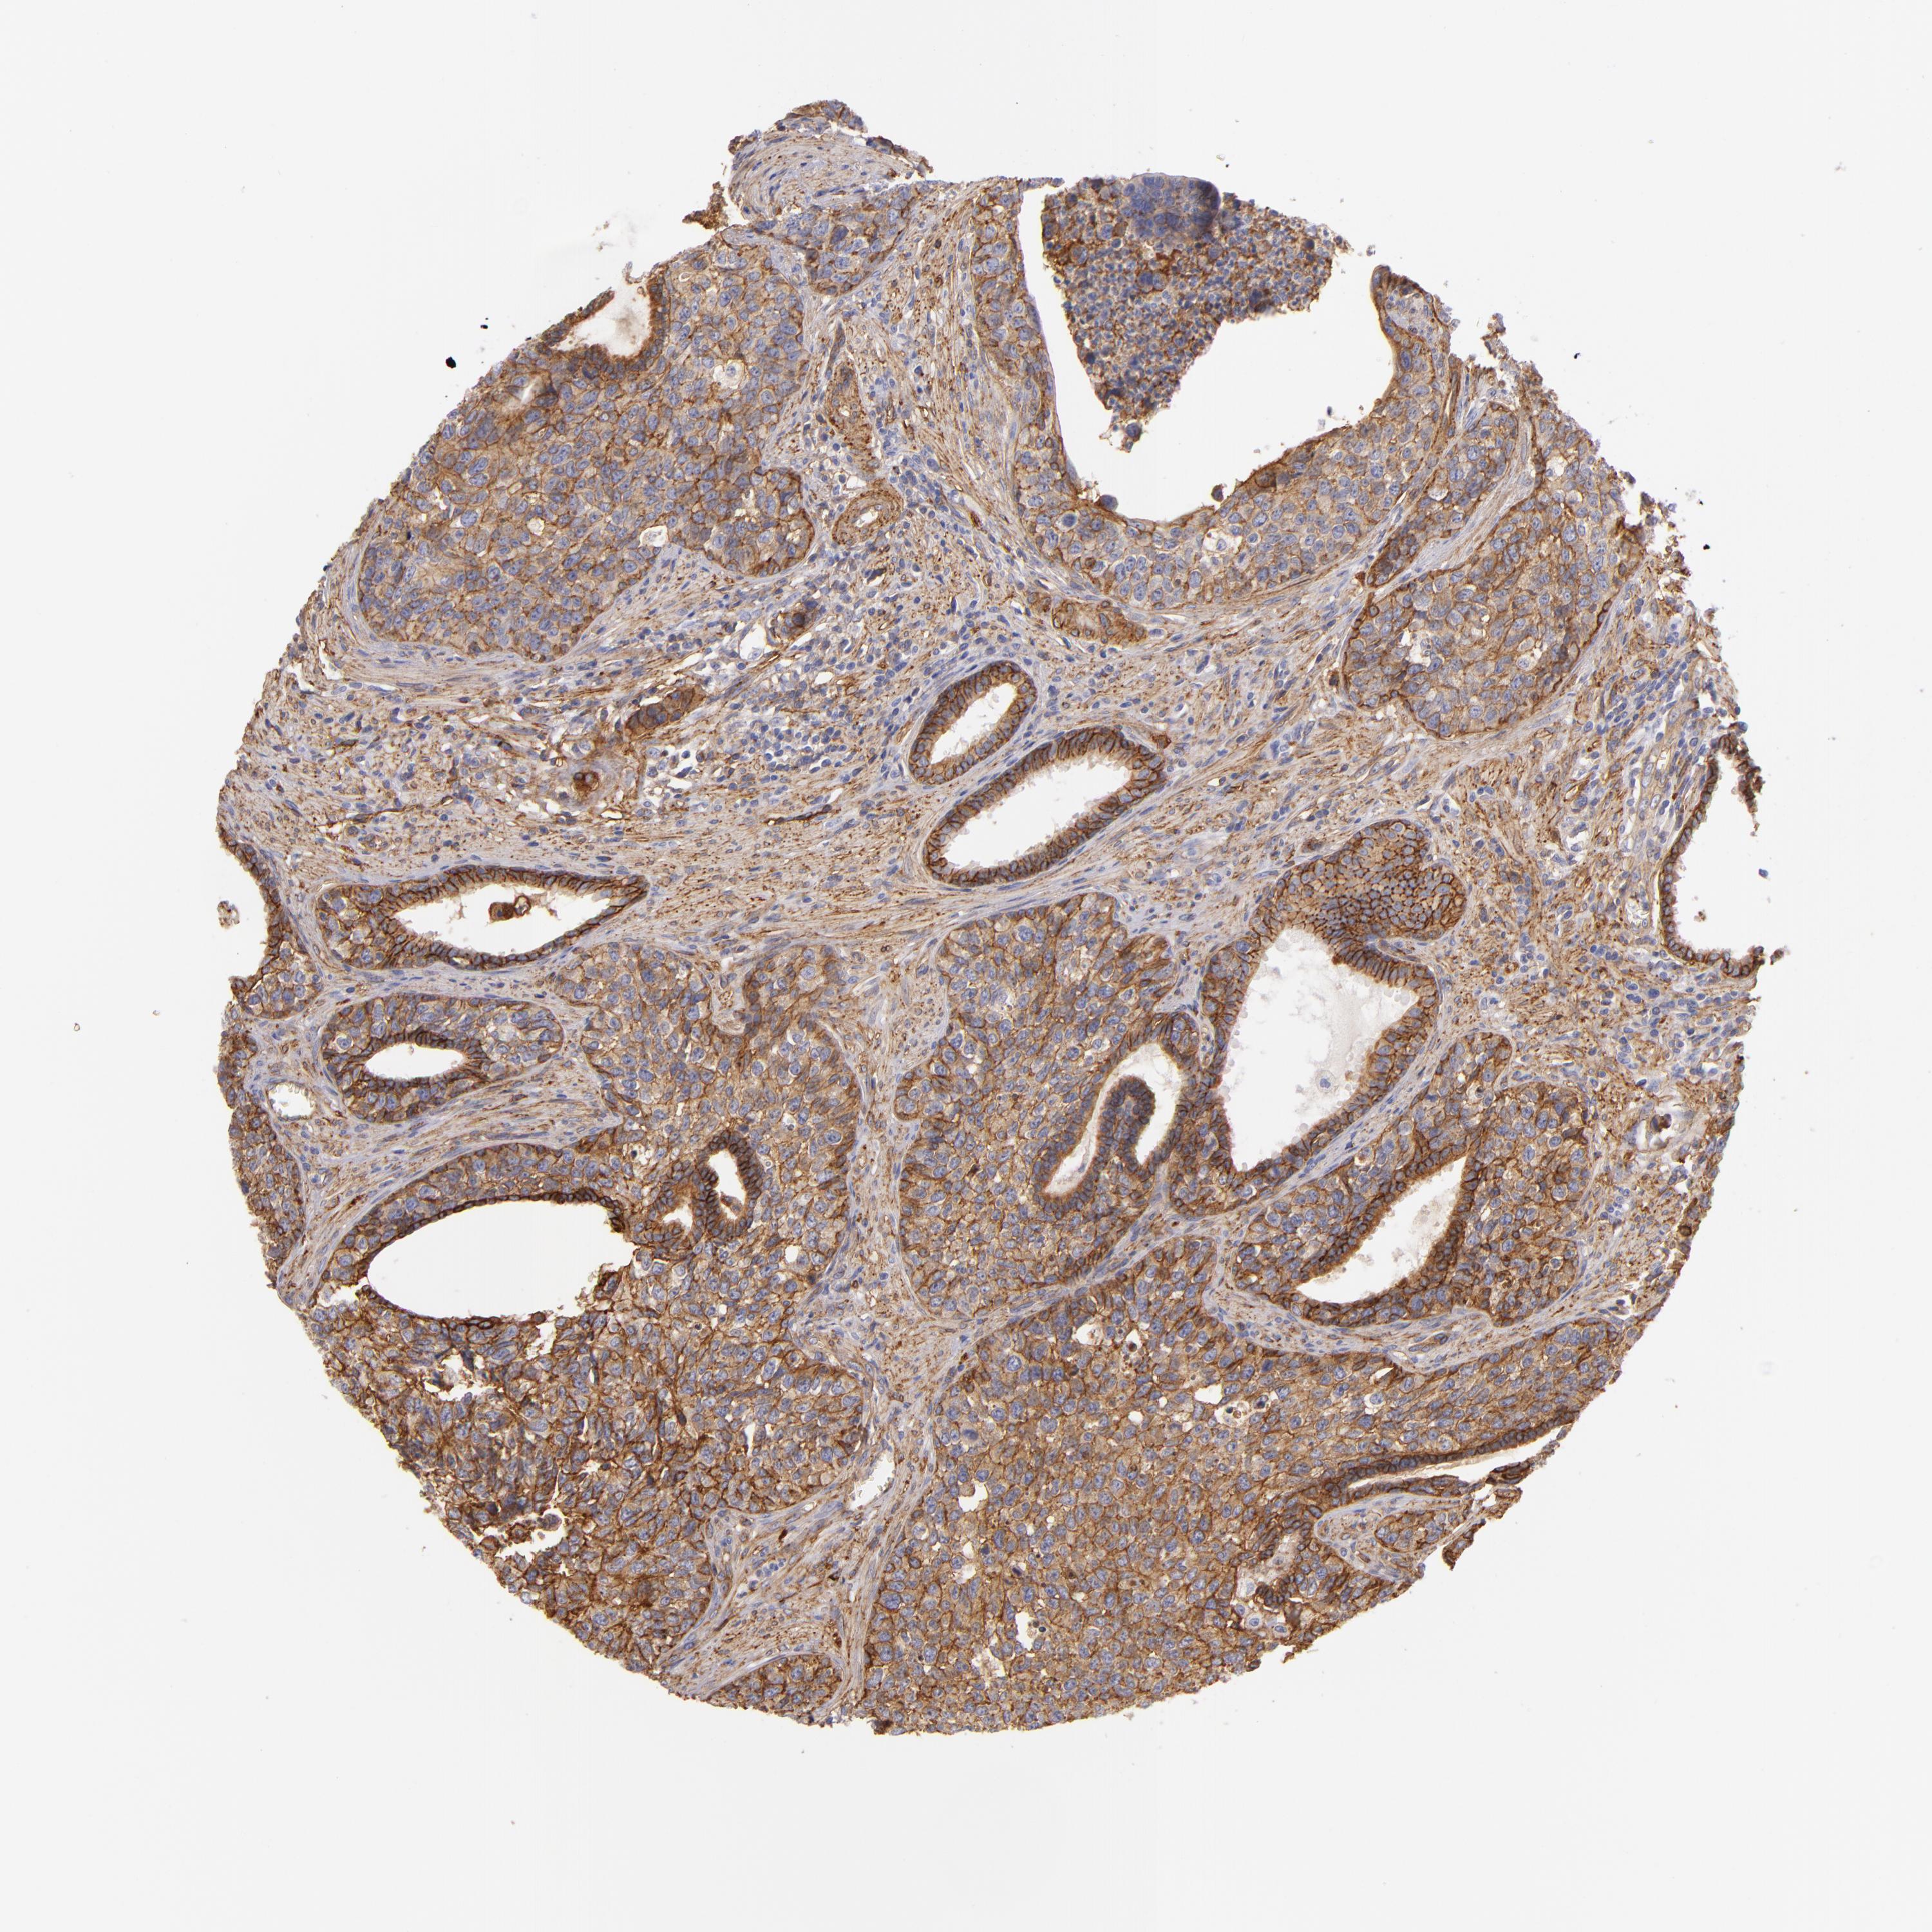

UROTHELIAL CANCER - Protein expressioni

A mouse-over function shows sample information and annotation data. Click on an image to view it in a full screen mode. Samples can be filtered based on level of antibody staining by selecting one or several of the following categories: high, medium, low and not detected. The assay and annotation is described here.

Antibody stainingi

Antibody staining in the annotated cell types in the current human tissue is reported as not detected, low, medium, or high, based on conventional immunohistochemistry profiling in selected tissues. This score is based on the combination of the staining intensity and fraction of stained cells.

Each image is clickable and will lead to virtual microscopy that enables deeper exploration of all samples and also displays staining intensity scores, fraction scores and subcellular localization as well as patient and tissue information for each sample.

Antibody HPA011906

Antibody CAB002428

Urothelial carcinoma, Low grade

Urothelial carcinoma, High grade

Adenocarcinoma, NOS